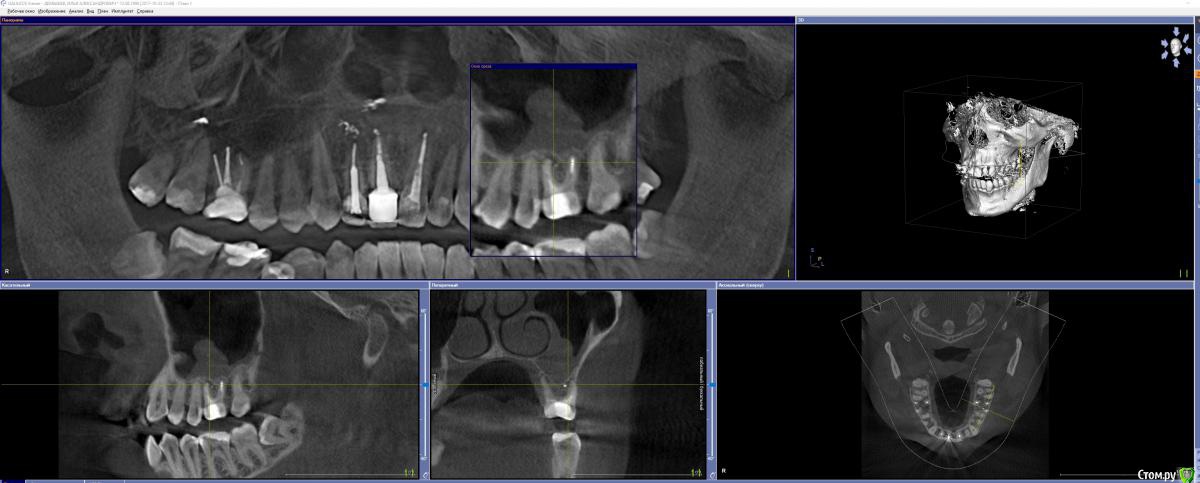

GoldJoker Опубликовано 3 декабря, 2017 Поделиться Опубликовано 3 декабря, 2017 Прошу совета знающих людей. Страдаю левосторонним гайморитом 5 лет, постоянные подтекания гноевидной слизи по задней стенке изредка выходящей через нос. На КТ 26 зуб киста, прикладываю 2 КТ с разницей в 1 год. Пролечли каналы под микраскопом, щечный канал был не пролечен ранее. Изначально зуб лечили 13 лет назад. Кистагранулема уменьшилась, проблема не ушла. Стоит ли ждать еще время либо нужно вырывать зуб, если вырывать. То будет ли сообщение посмотрите по снимку, если будет сообщение то чем его закрывать. И что с имплонтацией... Вообщем дайте совет что делать. КТ прикладываю. http://joxi.net/LmGp1LJueEWXb2- 2017 год фото http://joxi.net/82Q46k0Fj0XGKm- 2016 год фото https://yadi.sk/d/FB3RZAKD3QFND8- 2016 год полное кт 300мб. https://yadi.sk/d/rz8evJ5B3QFNDA- 2017 год полное кт 300мб. Ссылка на комментарий

Irouil Опубликовано 3 декабря, 2017 Поделиться Опубликовано 3 декабря, 2017 Я думаю, проблема в пазухе уже живёт отдельно от зуба. После перелечивания состояние сильно улучшилось, что в кости, так и в слизистой. Надо посмотреть как зуб реагирует на перкуссию (постукивания) и сравнить бы с тем, как он реагировал раньше. Создаётся впечатление, что повторное лечение оказалось успешным и зуб можно было бы не трогать, а прооперировать только саму пазуху. Если примете решение всё-таки удалять зуб, я бы подождал после этого два месяца, повторно снимок, если ситуация радикально не улучшается - эндоскопия пазухи, одномоментно синус лифт (по необходимости) и имплантация. Хотя тут возможны варианты. Сужу только по срезам, посмотреть всё КТ сейчас не могу. 1 Ссылка на комментарий

Irouil Опубликовано 7 декабря, 2017 Поделиться Опубликовано 7 декабря, 2017 (изменено) Все смешалось, кони, люди... Как-то Вы странно спрашиваете совета. Я бы Вас лечил так: 1) рекомендую досконально исследовать зуб, судя по срезам его лечение было успешным и удалять его поскорее я не советую (первичный очаг инфекции из зуба судя по всему изолирован качественной эндодонтией) 2) нужно оперировать пазуху, если соустье исправно (нужно кт, "нос дышит" не аргумент) - просто эндоскопически провести санацию. Доступ через нижний носовой ход или клыковую ямку (вероятнее второй вариант) 3) если удалите зуб и сформируется перфорация, способов закрыть соустье есть достаточно много, самый простой - щечным лоскутом (можно было бы закрыть только надкостницей - все бы закрывали, но пользуются обычно слизистыми или слизисто-надкостничными лоскутами). Под АБ защитой можно консервировать лунку (если есть шанс избежать синус лифта), а можно и не консервировать если все равно намечается синус лифт в будущем (этот вариант реальнее в Вашем случае). На имплантацию повлияет в первую очередь не тип лоскута (это решаемо) а костная поддержка мягких тканей 4) после удаления зуба ждите два месяца, дальше вилка: эндоскопия пазухи + синус лифт + имплантация или просто имплантация с/без синус лифтом/-а 5) Станислав Сысолятин спикер FESS дней у Андрея Лопатина от ЧЛХ, так что есть все шансы попасть к хорошему специалисту (если решитесь ехать к нему) Изменено 7 декабря, 2017 пользователем Irouil 1 Ссылка на комментарий

GoldJoker Опубликовано 24 декабря, 2017 Автор Поделиться Опубликовано 24 декабря, 2017 Все смешалось, кони, люди... Как-то Вы странно спрашиваете совета. Я бы Вас лечил так: 1) рекомендую досконально исследовать зуб, судя по срезам его лечение было успешным и удалять его поскорее я не советую (первичный очаг инфекции из зуба судя по всему изолирован качественной эндодонтией) 2) нужно оперировать пазуху, если соустье исправно (нужно кт, "нос дышит" не аргумент) - просто эндоскопически провести санацию. Доступ через нижний носовой ход или клыковую ямку (вероятнее второй вариант) 3) если удалите зуб и сформируется перфорация, способов закрыть соустье есть достаточно много, самый простой - щечным лоскутом (можно было бы закрыть только надкостницей - все бы закрывали, но пользуются обычно слизистыми или слизисто-надкостничными лоскутами). Под АБ защитой можно консервировать лунку (если есть шанс избежать синус лифта), а можно и не консервировать если все равно намечается синус лифт в будущем (этот вариант реальнее в Вашем случае). На имплантацию повлияет в первую очередь не тип лоскута (это решаемо) а костная поддержка мягких тканей 4) после удаления зуба ждите два месяца, дальше вилка: эндоскопия пазухи + синус лифт + имплантация или просто имплантация с/без синус лифтом/-а 5) Станислав Сысолятин спикер FESS дней у Андрея Лопатина от ЧЛХ, так что есть все шансы попасть к хорошему специалисту (если решитесь ехать к нему)Немного вывели материал в кость. Вокруг него небольшое потемнение. Правда что вокруг пломбировочного материала образуется фиброзная ткать. И это потемнение нужно считать ей а не оставшимся воспалением. Ссылка на комментарий